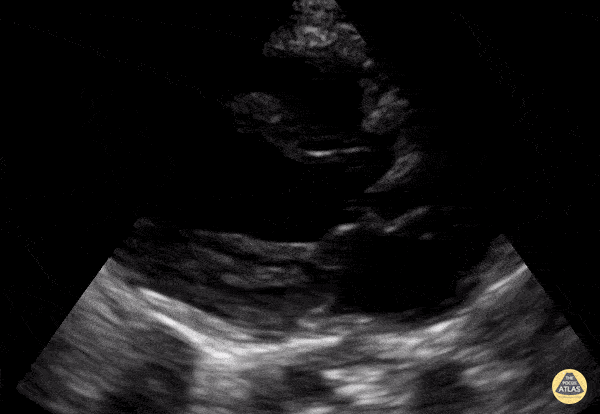

Normal Toddler PSLA. Contributor: Jaron Smith, MD, Phoenix Children's Hospital

https://www.thepocusatlas.com/pedscardiac